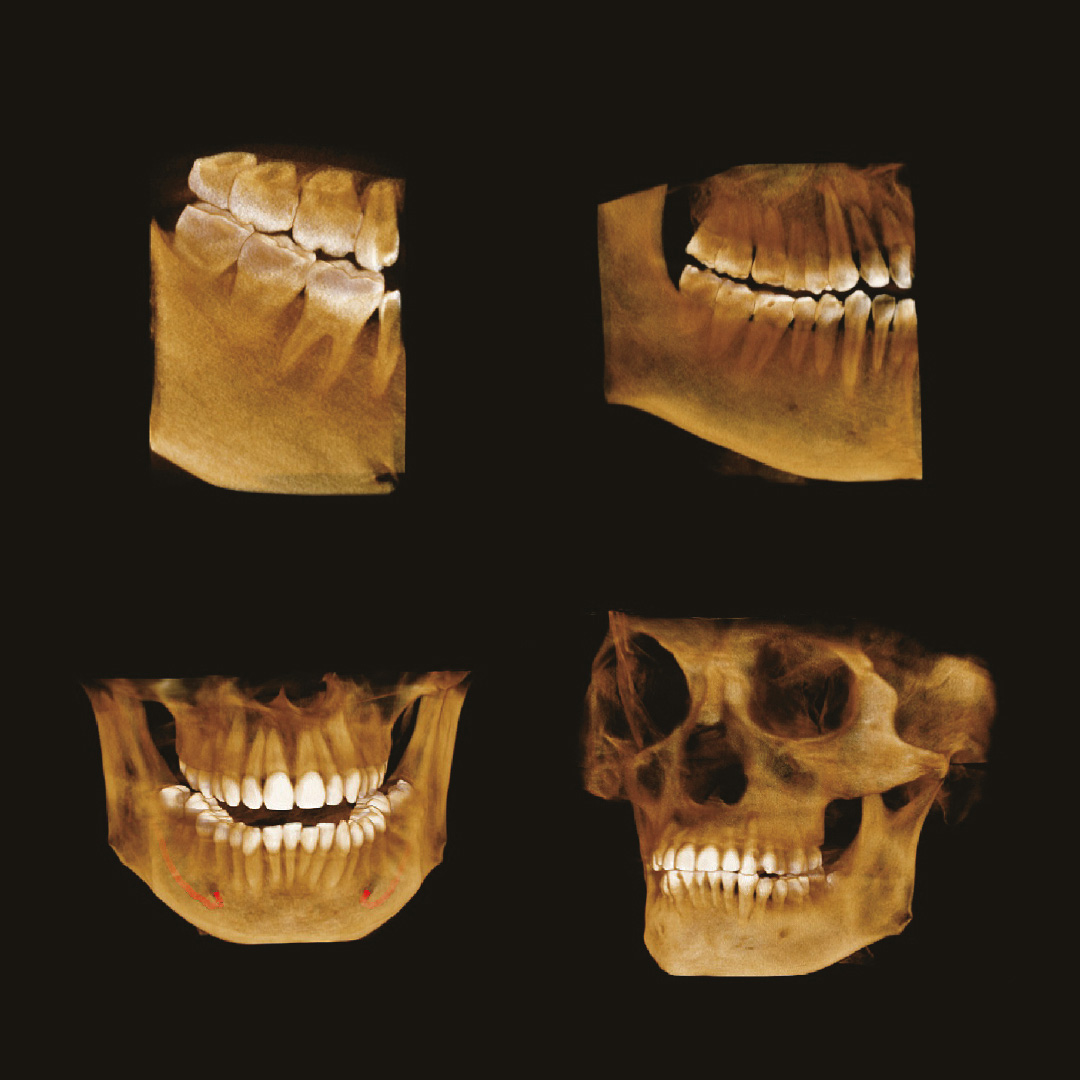

Если же ваша стоматологическая клиника располагается в жилом доме, помимо всего написанного выше, необходимо, чтобы дентальный томограф имел мощность излучения не выше 70кВ. Современные изготовители позаботились и об этом. На рынке представлено несколько моделей, которые удовлетворяют этим требованиям. Например, модель дентального томографа Papaya 3D (Plus) от компании Genoray имеет мощность излучателя 60~69 кВ и может располагаться в жилых помещениях, не принося вред жильцам и удовлетворяя санитарно-эпидемиологическим требованиям.